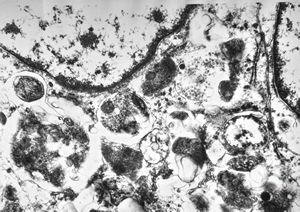

F, 7y. | molluscum contagiosum … virions

F, 7y. | molluscum contagiosum … virions